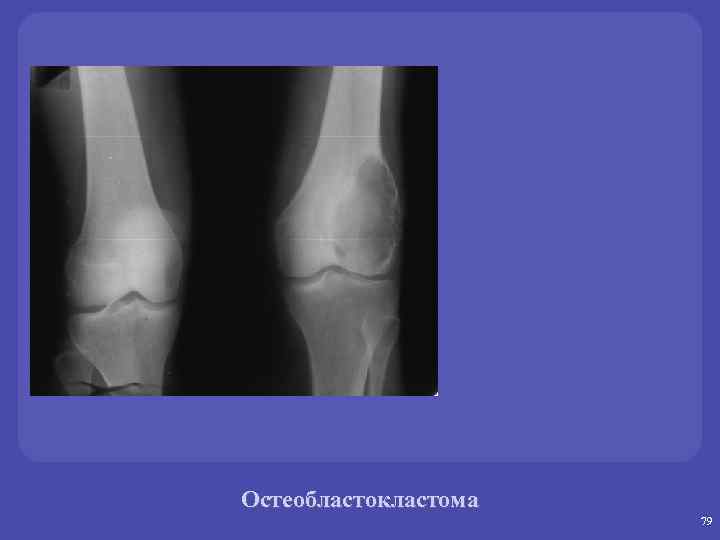

Остоебластокластомы. üГигантоклеточная опухоль. Микроскопически: одноядерные клетки (остеобласты), многоядерные гигантские клетки (остеокласты). üОпухоль собственно костной ткани, существующая как в доброкачественном, так и в злокачественном варианте. üЛокализация – дети - эпифиз, взрослые – метаэпифиз. Изолированно в диафизе не возникает. üФормы-пассивно –кистозные, активнокистозные, литические.

Остеобластокластома 79

Остеобластокластома 80

Остеобластокластома 81

Остеобластокластома 82